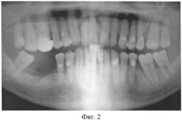

На фиг.2 - ортопантомограмма пациента перед операцией имплантации.Figure 2 - orthopantomogram of the patient before the implantation operation.

Диагноз: парадонтит 48 зуба средней степени тяжести, 3-4 стадии. Включенный дефект зубного ряда нижней челюсти справа. Фиг.2 - ортопантомограмма больного до лечения.Diagnosis: periodontitis of 48 teeth of moderate severity, 3-4 stages. Included defect of the dentition of the lower jaw on the right. Figure 2 - orthopantomogram of the patient before treatment.